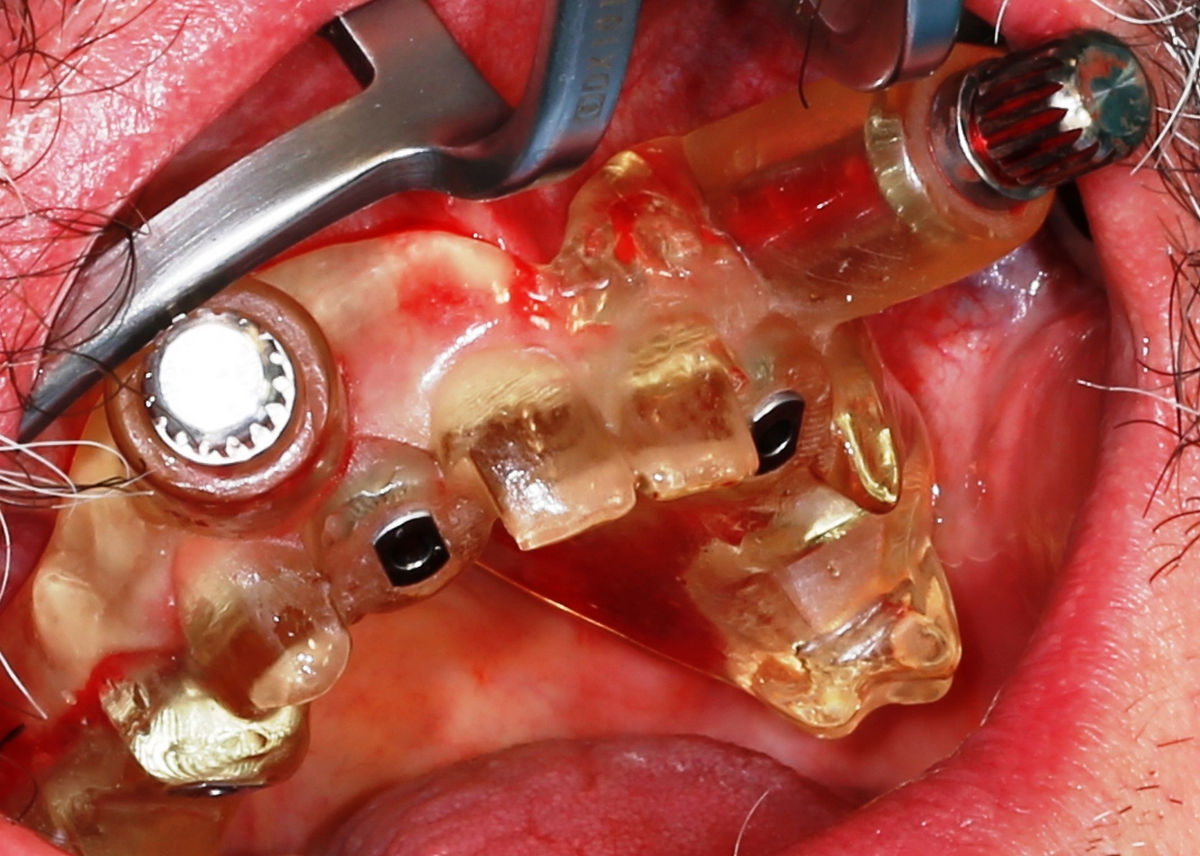

Chirurgia implantologiczna to temat wiodący 5 Sesji X Sezonu Practiculum Implantologii, która się odbyła 23-24 października 2020 roku. Bierze w nim udział 16 adeptów implantologii stomatologicznej. Zabiegi z udziałem Pacjentów jak zwykle poprzedziło omówienie i planowanie, tym bardziej, że zgodnie z planem wykonana została implantacja z wykorzystaniem szablonu chirurgicznego, który przygotowało laboratorium dentystyczne Wiligała Lab. Kursanci wykonywali szereg zabiegów implantologicznych i chirurgicznych oraz regeneracyjnych z zastosowaniem PRF, w tym sinus lift. Przeprowadzali je pod kierunkiem Lidera Umiejętności Implantologicznych dr n.med. Violetty Szycik, która wysoko oceniła wykonanie zabiegów.